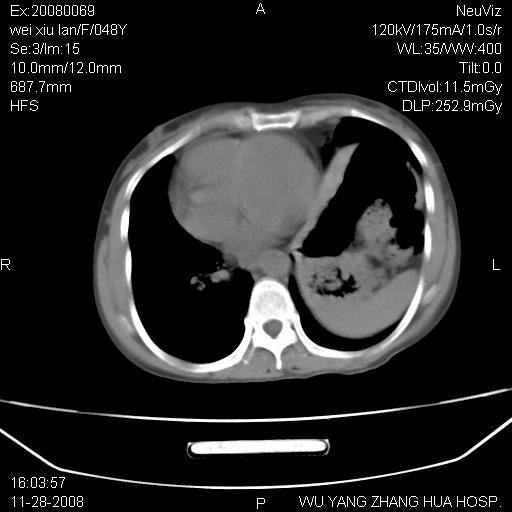

标题: CT16847:女,48岁,咳嗽,发热两日,平常偶有上腹部不适。 [打印本页]

标题: CT16847:女,48岁,咳嗽,发热两日,平常偶有上腹部不适。

左下肺不张、膈膨升,胸腔胃

1.左侧隔膨升

2.左下肺炎性改变

胃、脾脏及部分肠管明显升高,并压迫心脏移位,

首先考虑:左侧膈疝。

左侧胸腔内见胃肠及脾脏影

支持膈疝